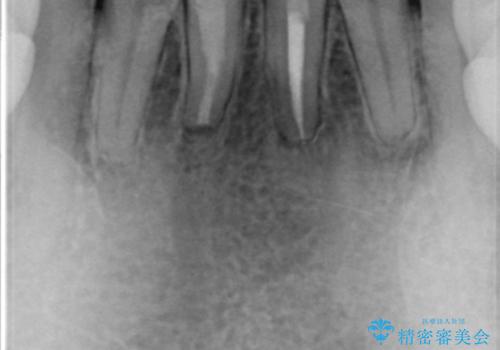

- 下の前歯の色が気になることを主訴に来院された患者様です。

下の前歯は金属の土台により黒くなり、隣の歯も神経が死んで暗く変色していました。

神経が死んでいる歯の根管治療を行った後、セラミッククラウンによる補綴治療を行いました。

※右下1の再根管治療もおすすめしましたがご希望されませんでした。

※下顎前歯部の叢生について矯正も提案致しましたが、ご希望されませんでした。